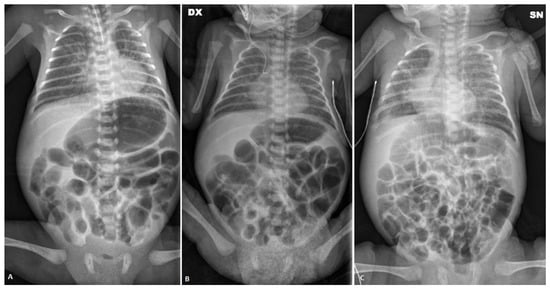

She was then transferred to our NICU to undergo percutaneous closure of the PDA performed at around 34 days of life, in the absence of postoperative complications. Despite the closure of the PDA, the subsequent attempt at enteral feeding was followed by abdominal distension initially attributed to reperfusion syndrome. Abdominal ultrasonography revealed no signs of pneumatosis and no intestinal and biliary tract abnormalities. Serial abdomen X-ray exams showed diffuse intestinal dilatation and no evidence of intra-abdominal free air (Figure 2A). Relevant abdominal distention persisted, and during this period, there was no spontaneous stool production. A contrast enema was performed using the nonionic dimer contrast agent iodixanol 320 (Visipaque) and showed dolichosigma exclusively. Barium enema and small bowel enema studies were performed, with normal results. Newborn metabolic screening and genetic tests for cystic fibrosis were negative. We found no hormone anomalies.

At around 56 days of life, in the suspicion of an intestinal motility disorder, therapy was started by nasogastric tube with amoxicillin–clavulanic acid at a dosage of 10 mg/kg twice a day, and at the same time, NAC rectal enemas were started twice a day. The execution of the enemas determined the emission of stools (normal color and consistency) but without improvement in abdominal distension.

On the 86th day of life (Figure 2B), postponed due to an episode of sepsis caused by Serratia marcescens, minimal enteral feeding (using breast milk) was started in association with the administration of NAC via a nasogastric tube. With the introduction of NAC treatment, there was a regularization of the frequency and consistency of the stools andan absence of clinically relevant abdominal distension (Figure 2C), which made it possible to reach full enteral feeding and weight gain. The infant was discharged home with full oral feeding on day 110.

Figure 2. Abdominal X-ray of patient P2 on the 36th day of life (A); persistent abdominal distension on the 86th day of life (B); and abdominal X-ray after the NAC treatment (C).